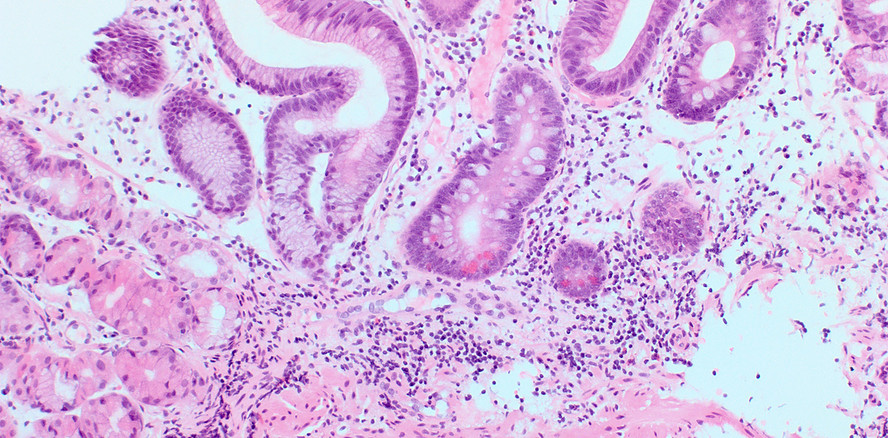

Damit einhergehende Beschwerden machen eine normale ausgewogene Ernährung nahezu unmöglich.15, 16 Die veränderte, nun pathogene Mundflora hat aber auch Einfluss auf sämtliche weitere Verdauungsschritte. Über den mikrobiell kontaminierten Speichel geraten Hefen und Bakterien in sämtliche Abschnitte des Gastrointestinaltrakts. Sowohl ­Candida als auch virulente Bakterien wie Porphyromonas gingivalis können problemlos die Säureschranke des Magens überwinden. Sie triggern chronische Entzündungen und Metaplasie der Magenschleimhaut (Abb. 5) und können sich danach im Dünn- und Dickdarm in das präexistente Mikrobiom integrieren.11 Als sogenannte „keystone Organismen“ mit selbst nur geringer Reproduktionsrate modulieren sie das Darmmilieu in Richtung eines dysbiotischen Mikro­bioms.18 Orale Pathogene wie Fusobacterium nucleatum und Porphyromonas gingivalis sind maßgeblich an der Induktion dysplastischer Epithelveränderungen und an der Progression der Adenom-Karzinomsequenz im Colon beteiligt (Abb. 6). Die Artenverarmung und das Ungleichgewicht inner­halb der Darmflora werden durch eine im Alter oft unzureichende Aufnahme von faserreicher Kost gefördert. Ballast­stoffe sind aber wesentlich, weil die Bakterien daraus kurzkettige Fettsäuren wie das stoffwechselfördernde Acetat, das entzündungshemmende Propionat und das die Darmbarriere stärkende Butyrat synthetisieren. Ein Ballaststoffmangel führt zu Resorptionsstörungen und lokaler Immundefizienz.2 Die Auswirkungen von altersbedingten Mastikationsstörungen und Zahnverlust gehen weit über ausschließlich orale Probleme hinaus. Schwerwiegende Folgen wie Malnutrition und die Progression systemischer und metabolischer Erkrankungen machen die Alterszahnmedizin zu einer wichtigen Disziplin für die Gesundheit im Senium. Die Erhaltung und Reetablierung einer artenreichen gesunden Mundflora, früh­zeitige Intervention bei fungalen und bakteriellen Entzündungen und im Bedarfsfall optimale prothetische und technische Versorgung zur Wiederherstellung der Kaufunktion sind Eckpfeiler einer gesunde Ernährung im höheren Alter.